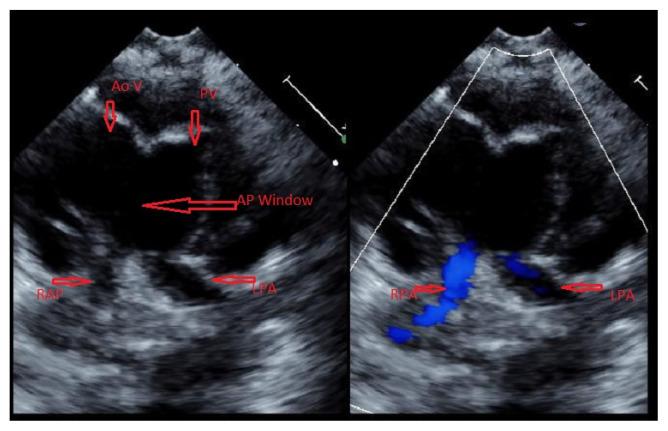

Uncommon Association of Aortopulmonary Window in a Patient with Complex Univentricular Heart and CHARGE Syndrome.

Kans J Med. 2021 Feb 12;14(1):48-50. doi: 10.17161/kjm.vol1414591. eCollection 2021.